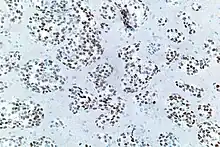

Thyroid transcription factor-1 (TTF-1) is a protein that regulates transcription of genes specific for the thyroid, lung, and diencephalon. It is also known as thyroid specific enhancer binding protein. It is used in anatomic pathology as a marker to determine if a tumor arises from the lung or thyroid. NKX2.1 can be induced by activin A via SMAD2 signaling in a human embryonic stem cell differentiation model.[7]

TTF-1 positive cells are found in the lung as type II pneumocytes and club cells. In the thyroid, follicular and parafollicular cells are also positive for TTF-1.

For lung cancers, adenocarcinomas are usually positive, while squamous cell carcinomas and large cell carcinomas are rarely positive. Small cell carcinomas (of any primary site) are usually positive. TTF1 is more than merely a clinical marker of lung adenocarcinoma. It plays an active role in sustaining lung cancer cells in view of the experimental observation that it is mutated in lung cancer.[11][12][13][14]

However others have found that TTF-1 staining is often positive in pulmonary adenocarcinomas, large cell carcinomas, small-cell lung carcinomas, neuroendocrine tumors other than small-cell lung carcinomas and extrapulmonary small-cell carcinomas.[16]

It is also positive in thyroid cancers and is used for monitoring for metastasis and recurrence.[17]